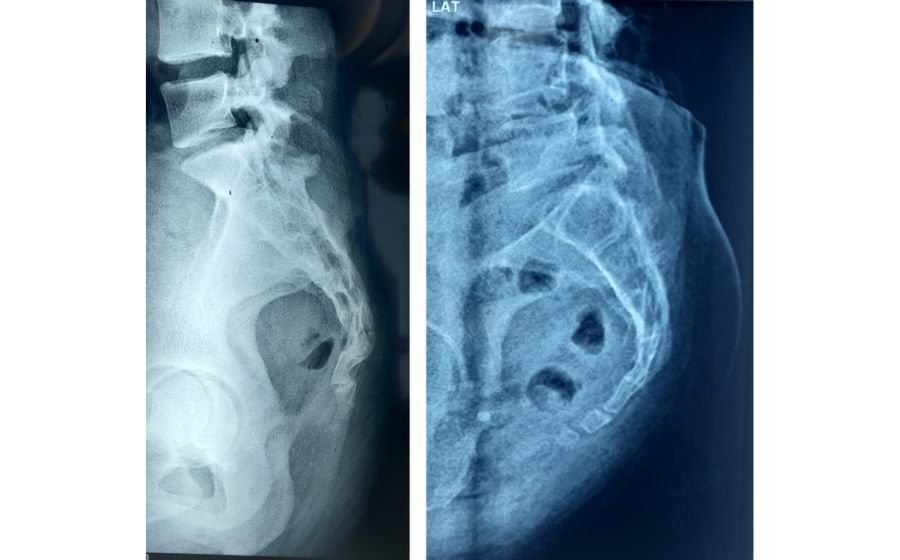

Spondylolisthesis

Spondylolisthesis occurs when one vertebra slips forward over the one below it, often due to aging, arthritis, stress fractures, or congenital weakness. This slippage can narrow the spinal canal and press on nerves, causing back pain, leg pain, tingling, or difficulty standing and walking. Diagnosis is made using X-rays and MRI to assess the degree of slip and nerve compression. Treatment includes physiotherapy, core strengthening, medications, and targeted injections. In cases with instability or persistent symptoms, minimally invasive or fusion surgery helps restore alignment, relieve nerve pressure, and improve long-term stability and mobility.